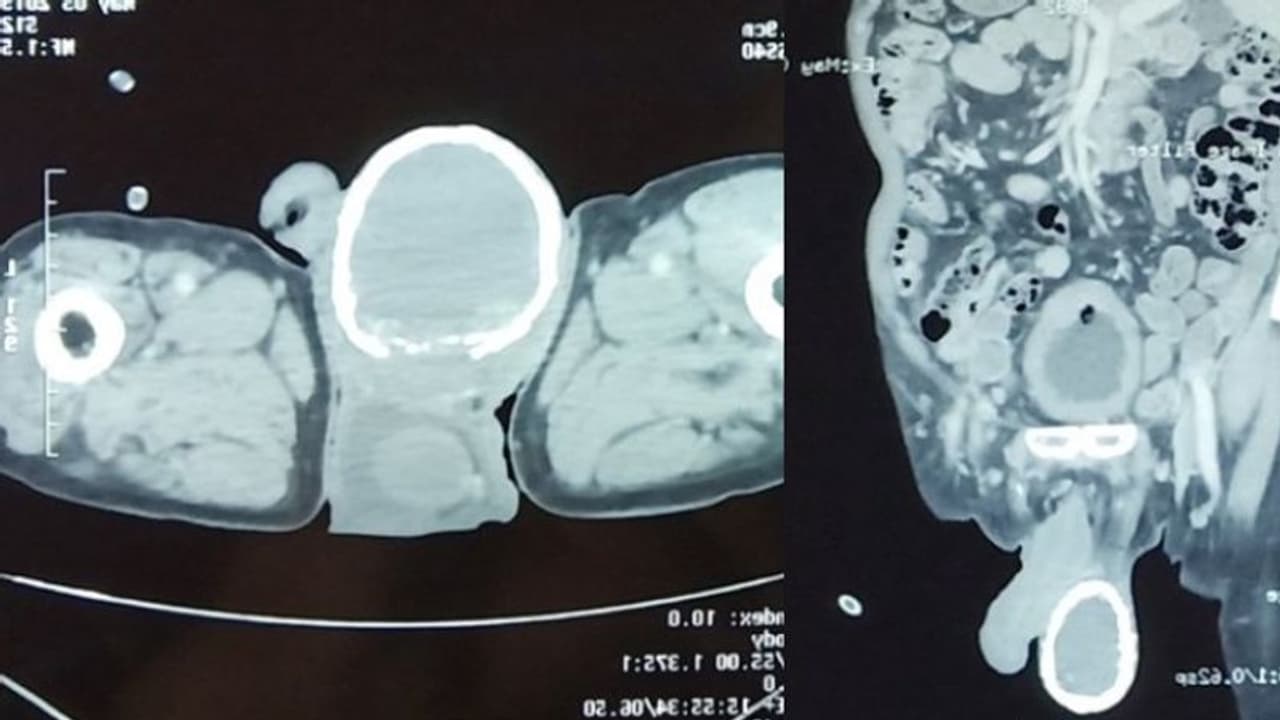

തുടര്ന്ന് നടത്തിയ സി ടി സ്കാനില് വൃഷണത്തില് വെള്ളം നിറഞ്ഞ 'hydrocele' എന്ന അപൂര്വ അവസ്ഥയാണ് രോഗിക്ക് എന്ന് സ്ഥിരീകരിച്ചു. കൂടാതെ വൃഷണത്തില് കാത്സ്യം അടിഞ്ഞ് ഒരു മുട്ടത്തോടു പോലെ രൂപപ്പെട്ടിരുന്നു. Calcification എന്നാണു ഇതിനെ പറയുന്നത്.